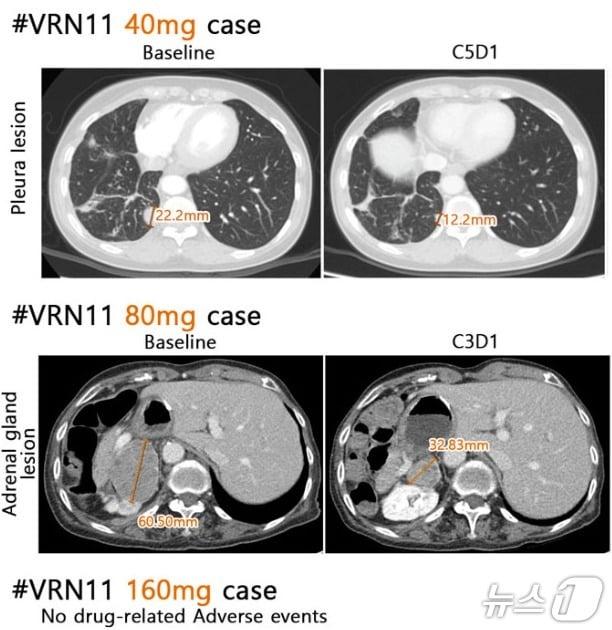

본문 이미지 - 보로노이 4세대 폐암 신약 후보물질 'VRN11' 용량별 투여 결과. 병변이 줄어 들고 별다른 부작용이 확인되지 않았다.(보로노이 제공)/뉴스1

보로노이 4세대 폐암 신약 후보물질 'VRN11' 용량별 투여 결과. 병변이 줄어 들고 별다른 부작용이 확인되지 않았다.(보로노이 제공)/뉴스1